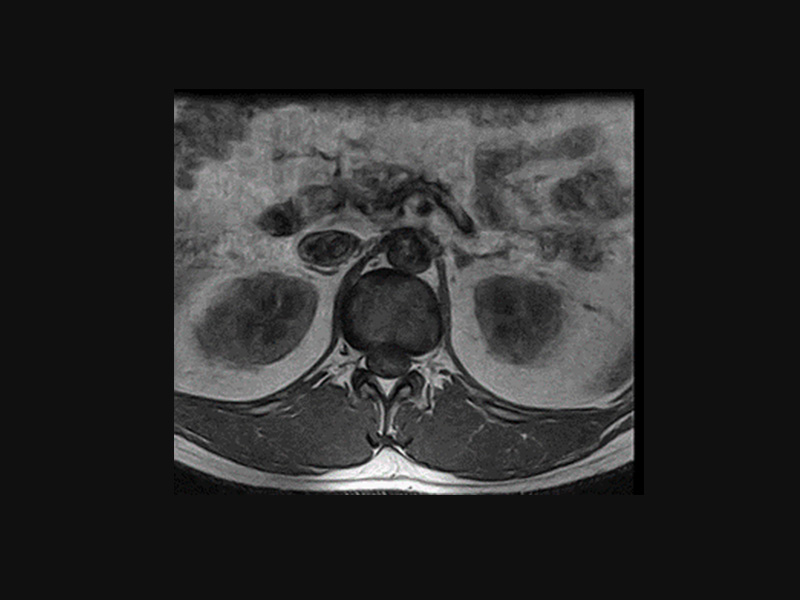

Klinické snímky